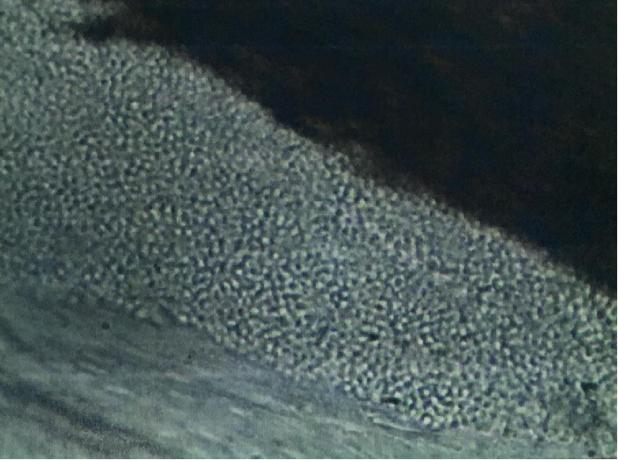

▲头发真菌镜检:发外镶嵌状孢子